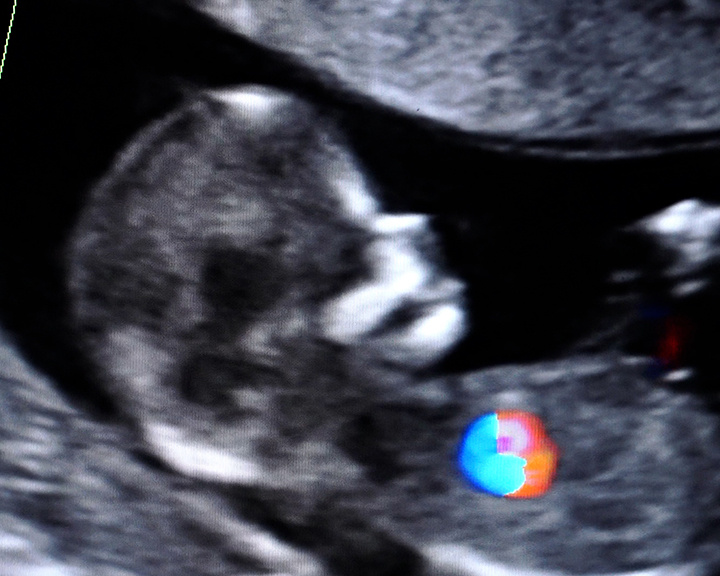

12 недель. Пол малыша пока остаётся загадкой. Это первый, самый важный скрининг беременности. Молодая мама уже сдала кровь и теперь ждёт результатов. Такой осознанный подход снижает риски и для неё, и для будущего ребёнка. Ежегодно от 15 до 20% беременностей сопровождаются осложнениями. Чтобы исключить угрозы, всех будущих мам направляют на пренатальную диагностику в Центр охраны здоровья семьи и репродукции. «Пренатальная» — значит «дородовая». Костромички сдают кровь на маркеры генетических аномалий и проходят ультразвуковую диагностику уже в первом триместре. Это позволяет убедиться, что малыш развивается правильно и не имеет хромосомных аномалий.

Все данные загружаются в специальную программу, которая сравнивает целый комплекс факторов и помогает рассчитать возможные риски. Только в прошлом году специалисты выявили 19 хромосомных аномалий, чаще всего — синдром Дауна и синдром Эдвардса. Ранняя диагностика особенно актуальна для женщин старше 35 лет. Сегодня они составляют около трети всех будущих мам, встающих на учёт. Но обследования на этом не заканчиваются. Во втором триместре проводится ещё одно УЗИ, чтобы исключить пороки развития, несовместимые с жизнью, и наконец успокоить будущих родителей.